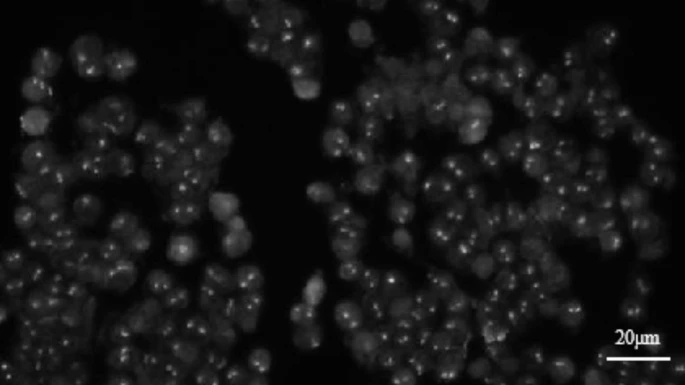

荧光原位杂交(FISH)技术是一种用于大分子识别的技术,它利用DNA或DNA/RNA双链的互补性。通过使用带有荧光标记的核苷酸标记的选定DNA链作为探针,这些探针与被检查的细胞和组织中的互补序列杂交,然后通过荧光显微镜或成像系统进行可视化。然而,FISH图像中细胞数量庞大和核酸序列无序排列带来了显著挑战。手动处理和分析这些图像不仅耗时,而且由于视觉疲劳,容易出错。为了克服这些挑战,研究提出了将医学成像与深度学习相结合的方法,开发了一种自动化的FISH图像检测系统。该系统包含一个算法,能够快速检测荧光斑点并捕获它们的坐标,这对于评估癌症诊断中的细胞特征至关重要。传统模型在处理荧光点的小尺寸、低分辨率和噪声方面表现不佳,导致性能显著下降。本文详细检查了这些问题,并提供了为什么传统模型会失败的见解。通过YOLO系列模型与传统方法的比较测试,证实了所提出方法在识别FISH图像中的荧光点方面的准确性更高

Jian, Z.; Song, T.; Zhang, Z.; Ai, Z.; Zhao, H.; Tang, M.; Liu, K. Deep Learning Method for Detecting Fluorescence Spots in Cancer Diagnostics via Fluorescence in Situ Hybridization. Sci Rep 2024, 14 (1), 27231. https://doi.org/10.1038/s41598-024-78571-4.